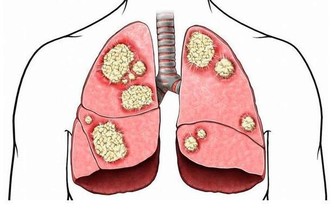

22點到凌晨3點是細胞生長速度最為旺盛的,也是荷爾蒙分泌的黃金時間段。若是錯過了此階段,就會影響到細胞的新陳代謝速度,加快了身體衰老。建議掌握正確的睡眠姿勢,不僅能讓氣血運輸到身體的各個部位,同時也能調氣養神,消除身心的疲勞感。常見的睡眠姿勢是仰臥,下肢和身體會處於伸直狀態,不能讓全身得到休息。腹腔壓力升高時,仰臥會讓人們出現胸口悶痛,而且不利於肺部得到氣血運行,影響了肺部功能。